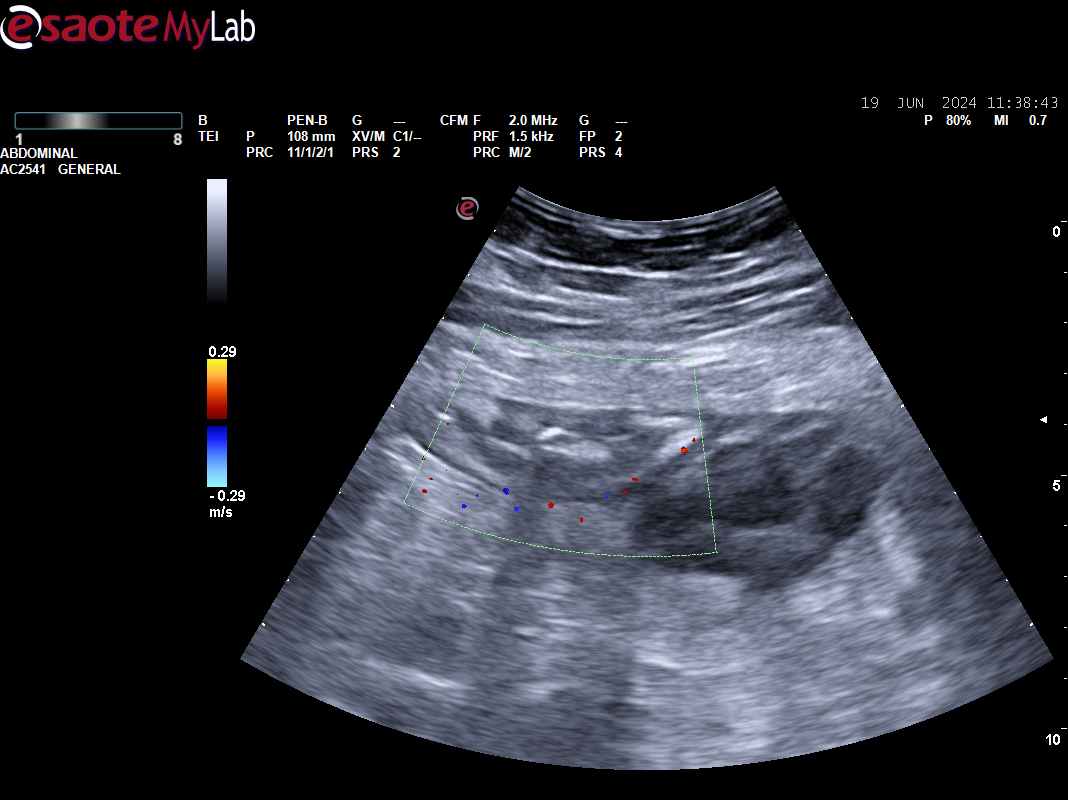

Paciente 2: vesícula distendida sin ecos en su interior, en línea media detectamos masa redondeada de 3-4 cm, Doppler positivo bajo proceso uncinado, dado dolor intenso no controlado se remite a urgencias e ingresa para estudio de posible masa pancreática.